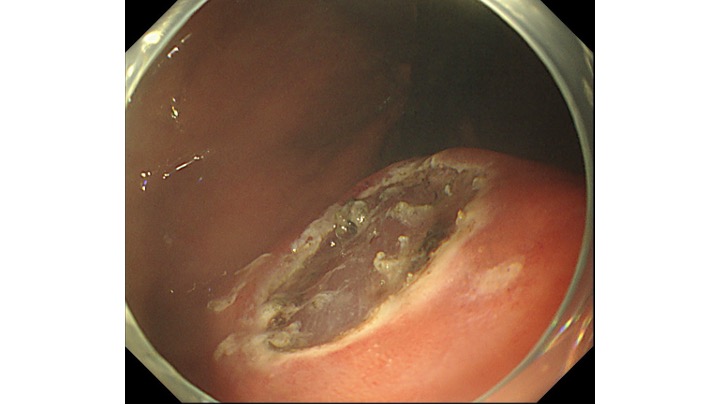

胃の上部の病変です。通常観察では、局在診断が困難な症例です。

拡大観察すると、領域(境界明瞭)のある癌がわかるかと思います。

通常観察にもどると、黄色の枠に病変があります。